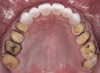

Fig 9. Occlusal view of posterior monolithic high-translucent zirconia restorations on the model.

Figure 9

A 40-year-old patient presented with the chief complaint: “My teeth are cracking, and I would like to have my original bite.” Dental findings included Class I occlusion with slight misalignment between teeth Nos. 8 and 9. Generalized severe occlusal wear and slight Class I mobility of teeth Nos. 23 to 26 were noted. Caries lesions were found on teeth Nos. 2, 4, 6, 8, 9, and 14 and abfraction lesions on teeth Nos. 4, 5, 10, 11, 13, 20, and 21. Figure 1 through Figure 3 depict the preoperative situation. Full-mouth rehabilitation was suggested. The goals for the restorative treatment were management of erosive etiology, conservation of tooth structure, and long-term protection of the restorations. A diagnostic wax-up was instrumental in determining functional and esthetic treatment goals and establishing new anterior guidance (Figure 4). A comprehensive, step-by-step treatment approach was applied, which, after periodontal pretreatment, caries control, and provisionalization, included definitive preparation (Figure 5) and restoration of the maxillary anterior teeth to establish anterior occlusal guidance. CAD/CAM–fabricated full-contour monolithic high-translucent zirconia crowns (Katana™ UTML Ultra Translucent Multi-Layered, Kuraray Noritake Dental, kuraraynoritake.com) were fabricated (Figure 6 and Figure 7) and cemented with self-adhesive resin cement (Panavia SA, Kuraray Noritake Dental). Figure 8 demonstrates the cemented anterior crowns and refined conservative preparations of posterior teeth, which were performed with minimal tooth-structure removal. High-translucent monolithic zirconia onlays and crowns were fabricated (Katana Zirconia UT, Kuraray Noritake Dental) (Figure 9 to Figure 12). The posterior restorations were adhesively bonded following the APC zirconia-bonding concept. APC-Step A involved air-particle abrasion with 50-μm aluminum oxide at 1.5 bar with a chairside microetcher (Figure 13), followed by application (APC-Step P, Figure 14) of a special ceramic primer (ClearfilTM Ceramic Primer, Kuraray Noritake) with adhesive phosophate monomers (MDP). Relative moisture and contamination control was achieved with cotton rolls and retraction cords. Rubber dam placement, which is always preferred, was difficult in this situation. The enamel surfaces of the abutment teeth were selectively etched (Figure 15) with 35% phosphoric acid (K-Etchant Gel, Kuraray Noritake Dental) and the dentin conditioned (Figure 16) with a self-etch dentin primer (Panavia V5 Tooth Primer, Kuraray Noritake Dental). A dual-cure adhesive resin (Panavia V5 Paste Universal, Kuraray Noritake Dental) was dispensed directly into the restorations with an automix syringe. The restorations were inserted, and excess cement was carefully removed (Figure 17 and Figure 18) before light polymerization (Figure 19). Postoperative views depict the treatment outcome (Figure 20 to Figure 22).